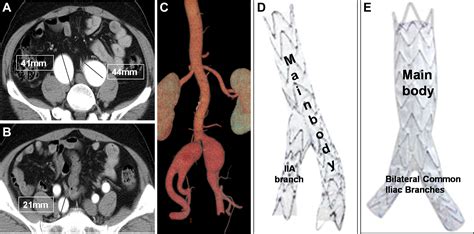

• Endovascular Repair: This minimally invasive procedure involves inserting a stent-graft through a small incision in the groin and guiding it to the site of the aneurysm. The stent-graft reinforces the weakened artery wall and prevents rupture.

• common iliac artery aneurysm size

• iliac artery aneurysm repair

Endovascular repair of bilateral common iliac artery aneurysms using ...

2781×2092